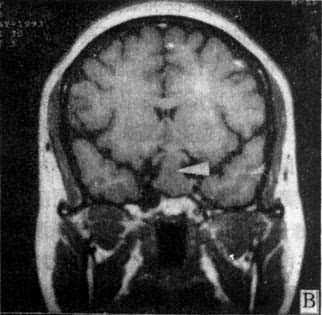

图5-1-6 MRI扫描SE序列图像 在矢状面(A)和冠状面(B)T1WI可见垂体肿块向鞍上延伸,呈等信号区(→);在横断面T1WI(C)和T2WI(D)上分别可见左枕和右基底节区脑梗塞灶呈低和高信号区(→);在矢状面T1WI(E)和横断面T2WI(F)上,可见基底动脉瘤环形影,其内为低信号和高信号区,高信号区为瘤内血栓形成(→) 七、颅内感染 颅内感染的病种很多,包括化脓性、结核性、病毒性和感染,以及脑寄生虫病。 (一)化脓性感染 化脓性脑膜炎早期CT扫描常无异常发现,脑膜粘连可出现脑室积水。并发硬膜下或外积脓时,在脑凸面或大脑镰旁可见新月形或梭形低密度灶,脓肿壁明显增强。脑脓肿早期CT表现为边缘模糊的低密度灶,伴有占位效应,代表急性脑炎期。脓肿形成期在大片低密度区内可见等密度环,壁薄和均匀性环形强化;产气杆菌感染,脓腔内可出现气泡或液面。CT可明确脓肿的部位、大小、数目和多房性;协助脓腔穿剌引流,并动态观察其发展和演变过程。目前脑脓肿的死亡率已由过去的36%~53%下降接近为零,这是由于CT的早期诊断和精确定位,配合临床及时准确治疗的结果。 (二)结核性感染 结核性脑膜炎的脑底渗出或肉芽增生,在CT上可表现为脑底池广泛或局灶性增强。结核瘤则出现等或混杂密度灶,可有钙化,均匀或环形强化。 (三)病毒性感染 单纯疱疹病毒性脑炎,CT表现为颞区低密度灶,边界模糊或清楚,占位效应轻,无增强。散发性脑炎可由多种病毒感染引起,CT上显示脑内散在性低密度灶,有时CT扫描阴性。 (四)真菌性感染 自然界普遍存在着真菌,当机体免疫或能低下时,常易罹患真菌感染,常见者有新形陷球菌、毛霉和茀状菌等。CT表现为脑炎、脑膜炎、肉芽肿、囊肿、脑出血或脑梗塞。真菌性肉芽肿呈等或高密度灶,灶周有脑水肿,增强CT呈大小和数目不等的强化结节,类似脑转移瘤的CT改变。 (五)脑寄生虫病 脑囊虫病典型CT表现为多发性小囊,囊壁或囊内的致密小点代表虫体的头节;散在性小圆形钙化点则表示死亡变性的囊肿;有时二者同时存在提示重复感染。脑血吸虫病急性脑炎型CT表现为低密度脑不肿区;慢性肉芽肿型则表现为强化结节,其形状、大小和数目不一。脑包虫病CT表现为巨大脑内囊肿,边界清楚,CT值类似水,周围无水肿。 CT扫描阴性的颅内感染性疾病例如脑膜炎和病毒性脑炎等,MRI常可获得进一步的证实。 八、其他脑疾病 (一)变性脑病 大脑变性脑病常见的老年性痴呆和多发脑梗塞性痴呆,CT扫描可见幕上脑室普遍性扩大,脑沟增宽,对称或非对称性,血管性痴呆尚可见多发性新老梗塞灶存在。 小脑和脑干变性疾病常见的有橄榄-脑桥-小脑萎缩和Marie共济失调,CT显示第四脑室扩大,小脑上沟增宽,后颅凹脑干周围脑池扩张。 基底节变性疾病有Wilson病、Parkinson病和CO中毒等,CT上显示脑室扩大以侧脑室前角扩大为明显,脑底池和外侧裂池增宽,脑基底节区有时可见对称或非对称性低密度灶。 (二)脱髓鞘脑病 先天性髓发育不良或称为脑白质营养不良,可见于异染性脑白质营养不良、类球状细胞白质营养不良、肾上腺脑白质营养不良等。CT表现脑白质对称性密度减低,与脑皮质的对比鲜明。获得性髓鞘脱失又称为脑白质病,常见有多发性硬化和皮质下小动脉硬化性脑病等,CT表现为脑室周围散在性斑片或带状低密度灶,伴有程度不同的脑萎缩。 (三)先天性畸形 脑膜(脑)膨出CT可见颅骨缺损,自缺损处突出一液性软组织包块,有的包块内有脑组织。胼低体发育不全显示双侧侧脑室扩大并分离,第三脑室扩大向上前移位于分离侧脑室之间,有的合并脂肪瘤或囊肿。Chiari畸形上CT可见小脑扁桃体下疝;有时伴有脑干、小脑和第四脑室延长下疝及脑积水改变,可合并脊髓空洞症、脑膜膨出及其他脑脊髓畸形。 (四)新生儿脑病 新生儿窒息CT可见弥漫性脑水肿、颅内出血或脑室内外积水。新生儿颅内出血由于产伤或缺氧所引起,出血于硬膜下或硬膜外腔、蛛网膜下腔、脑和脑室内,而以室管膜下出血具有特征性,CT表现沿脑室壁出现高密度线形影,后期遗留交通或非交通性脑积水。 MRI对许多变性脑病、脱髓鞘脑病和先天性畸形能够比CT提供更多的信息资料,可作为CT扫描诊断的补充。 九、脊柱和脊髓疾病 (一)椎管狭窄 椎管狭窄分为骨性和软组织狭窄,骨性椎管狭窄又分为中心型狭窄和周围型狭窄,后者指侧隐窝和椎间孔狭窄。先天性椎管狭窄常伴发于骨发育不全;获得性椎管狭窄可由骨折、炎症、肿瘤和退行性变引起,临床上出现一系列脊髓、脊神经和营养血管的压迫症状。横断面CT扫描可直接观察椎管狭窄变形,测量椎管大小并探明引起椎管狭窄的病因。 (二)椎间盘脱出CT扫描可直接显示突出于椎管或椎间孔内的软组织块影,与椎间盘相连或游离于椎管内,硬膜囊受压变形,硬膜外脂肪层变薄或消失,脊神经根增粗或湮没。椎间盘性变性显示变扁变形,向周围膨出,或出现气体(直空现象)。MRI上显示更为清楚。 (三)脊髓疾病 脊髓损伤急性期可见脊髓出血、水肿、受压、移位、挫伤或断裂;慢性期可见脊髓软化、萎缩、囊变或空腔化。脊髓肿瘤位于髓内者多为星形细胞或室管膜瘤,髓外硬膜内者多为脊膜或神经纤维瘤,硬外肿瘤以转移瘤常见。脊髓造影配合CT扫描才能对椎管内肿瘤作出正确的定位诊断。先天性畸形常见有脊髓空洞症、脊髓纵裂和脊髓血管畸形等,后者需行增强CT扫描。可显示脊髓表面扩张扭曲的血管影,并能确定血管畸形在椎管内大致伸延的范围。 MRI的软组织分辨率比CT高,矢状面扫描图像上可直观地显示脊髓病变的全貌及与周围组织结构的关系,是当今诊断脊髓疾病的最佳选择。 (责任编辑:泉水) |